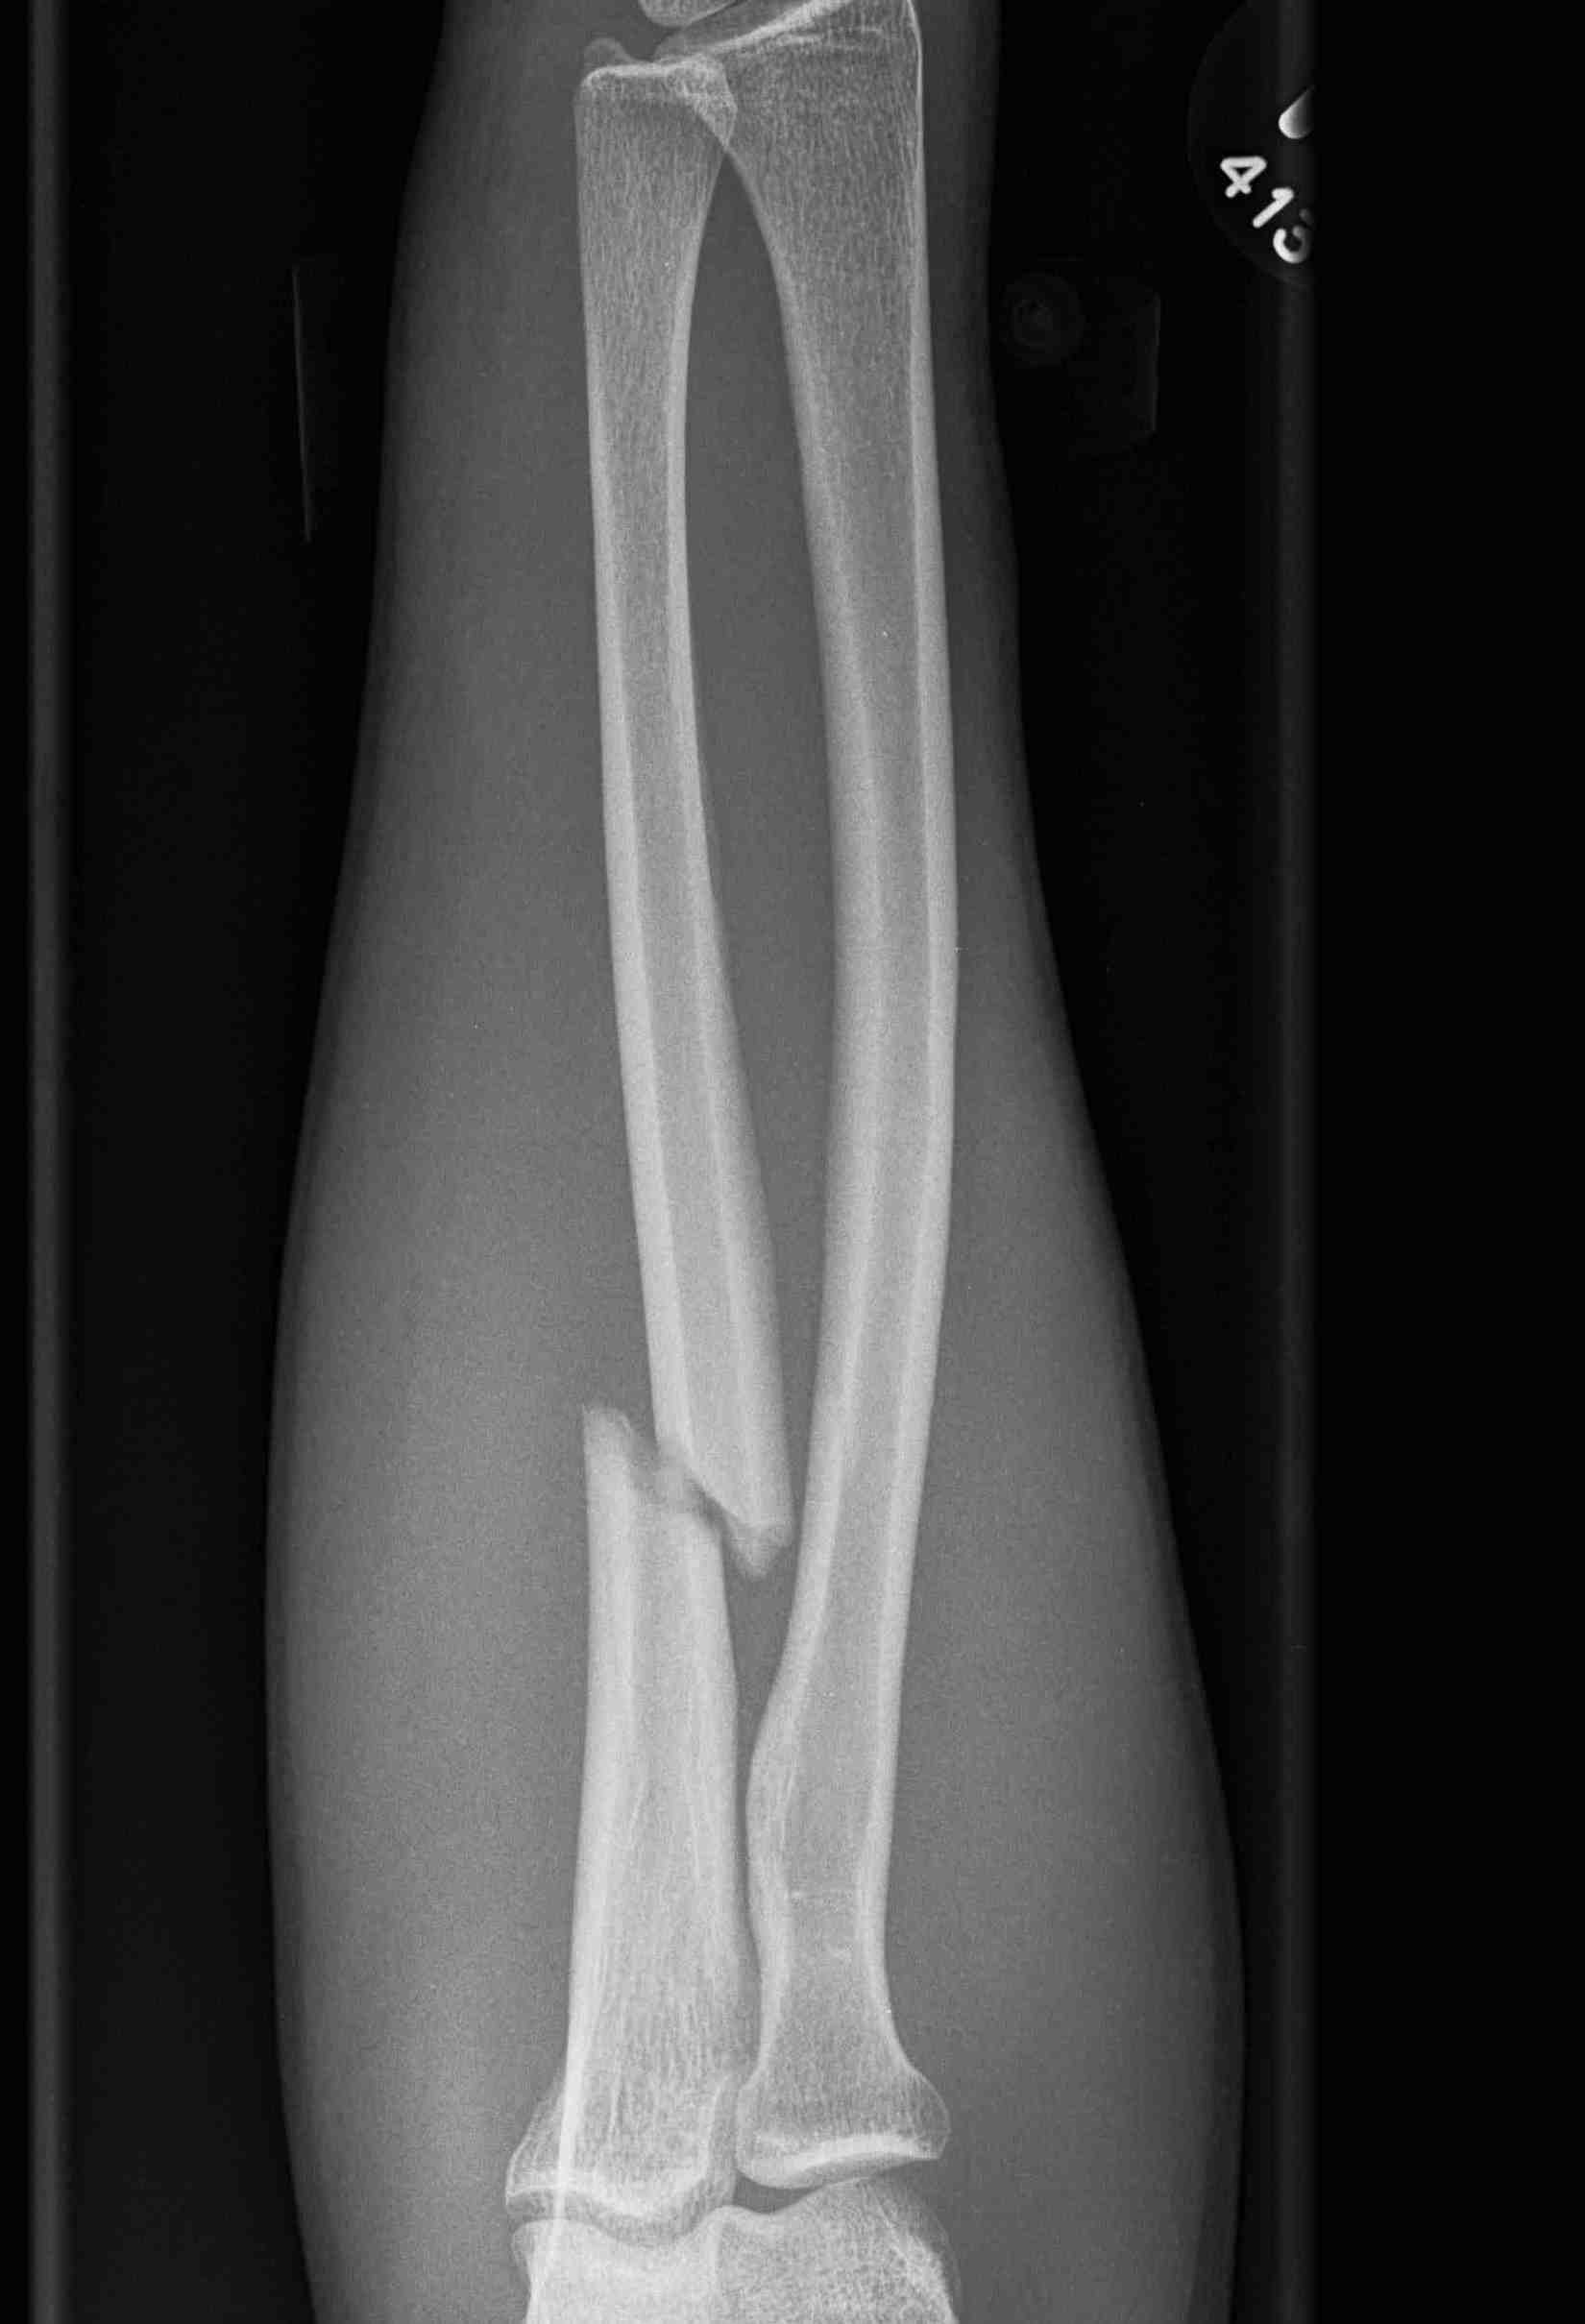

Midshaft / middle 1/3

Proximal - beware Monteggia / radial head dislocation

| Distal 1/3 | Middle 1/3 | Proximal 1/3 |

|---|---|---|

| Higher nonunion rates | Beware Monteggia / radial head dislocation | |